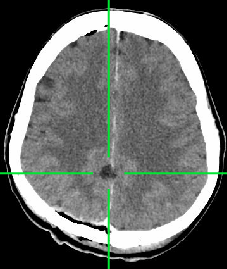

Spotāns intracerebrāls saasiņojums (hematoma)

Redzams saasiņojums smadzeņu vielā pirms operācijas

Pēcoperācijas attēls - saasiņojums no smadzenēm evakuēts